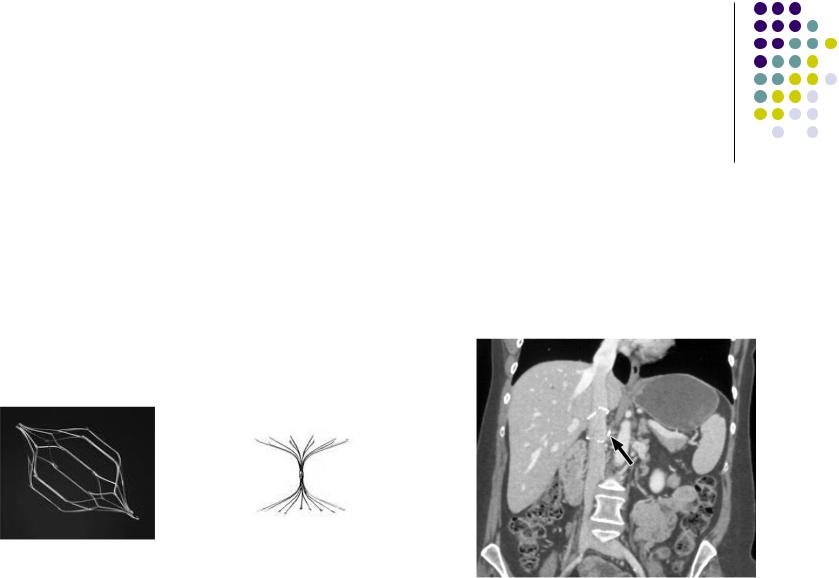

Варианты тромбэктомий при ТГВ

Прямая

Непрямая

-имплантация кава-фильтра.